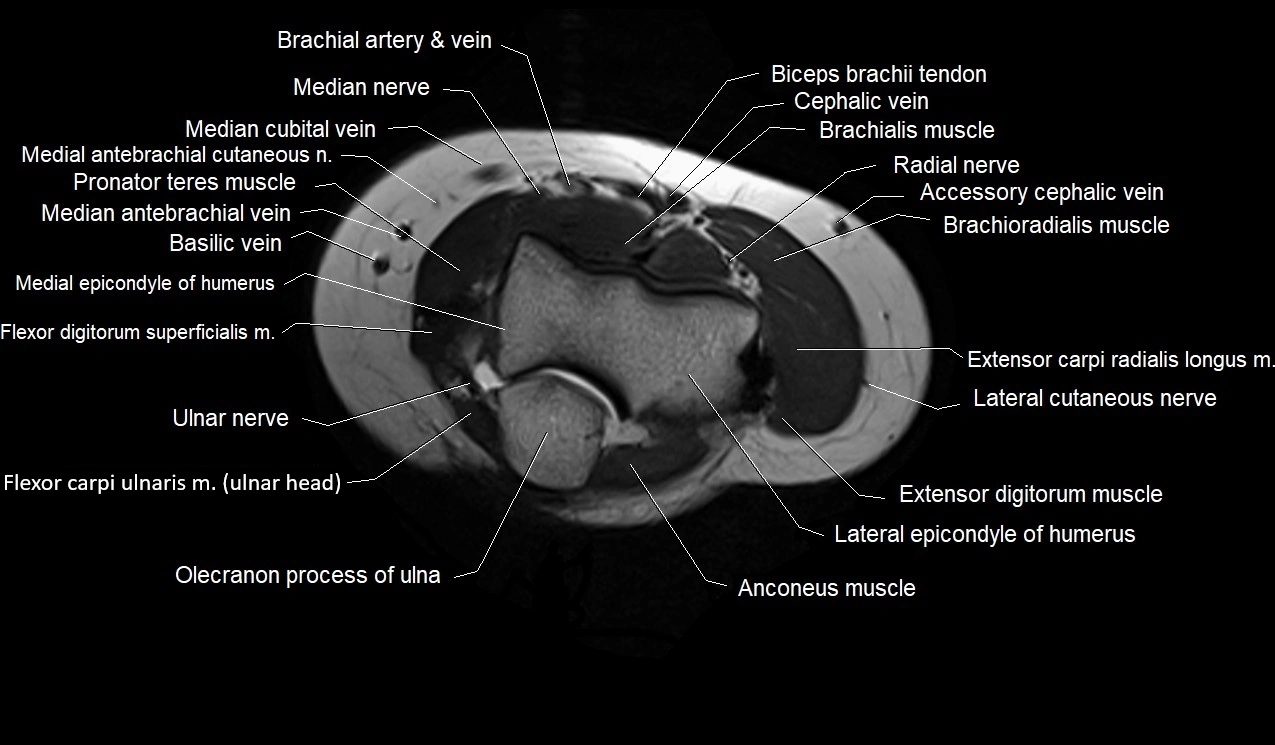

image

MRI images